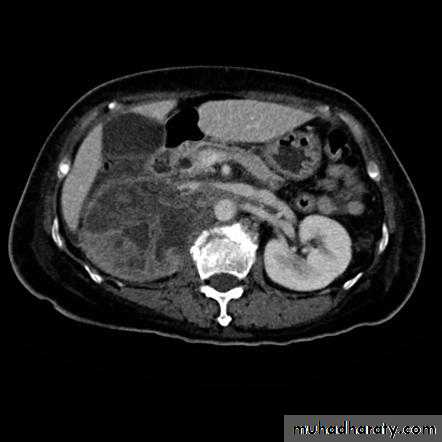

Normal CT scan of abdomen